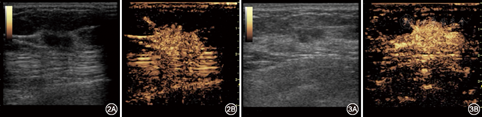

常规超声BI-RADS分类、CEUS预测模型、常规超声BI-RADS分类+CEUS预测模型及调整后BI-RADS分类诊断的敏感度、特异度、准确性、阳性预测值、阴性预测值分别为86.1%、65.1%、74.7%、67.4%、84.8%;88.9%、76.7%、82.3%、76.2%、89.2%;80.6%、86.0%、83.5%、82.9%、84.1%;97.2%、76.7%、86.1%、77.8%、97.1%(表1)。以病理结果为金标准,常规超声BI-RADS分类、CEUS预测模型、常规超声BI-RADS分类+CEUS预测模型及调整后BI-RADS分类ROC曲线下面积分别为0.756、0.828、0.833、0.870。组间两两比较,仅调整前、后BI-RADS分类差异有统计学意义(Z=2.322,P<0.05)(图1,图2,图3)。

本研究应用CEUS预测模型联合及调整常规超声BI-RADS分类两种方法鉴别乳腺肿块良恶性,结果显示,常规超声BI-RADS分类+CEUS预测模型诊断效能较单一应用常规超声BI-RADS分类及CEUS预测模型未见明显优势,ROC曲线下面积分别为0.833、0.756、0.828,差异均无统计学意义;而调整后BI-RADS分类相较其他三种方法可提高肿块良恶性诊断的正确率,诊断效能最高,ROC曲线下面积为0.870,且与常规超声BI-RADS分类比较差异有统计学意义。此外,虽然调整后BI-RADS分类的特异度虽略低于常规超声BI-RADS分类+CEUS预测模型,但其敏感度及正确性最高,分别达97.2%、86.1%,更适用于乳腺癌早发现、早诊断、早治疗的临床原则,有利于乳腺癌的预后和提高患者的生存质量。调整后24个良性肿块降为3类,可以短期随访代替穿刺活检,18个恶性肿块升为5类,使肿块诊断更加明确,而BI-RADS 4类肿块降至34个,使57.0%(45/79)肿块避免了穿刺活检,且仅有3.8%(3/79)肿块发生漏诊、误诊。